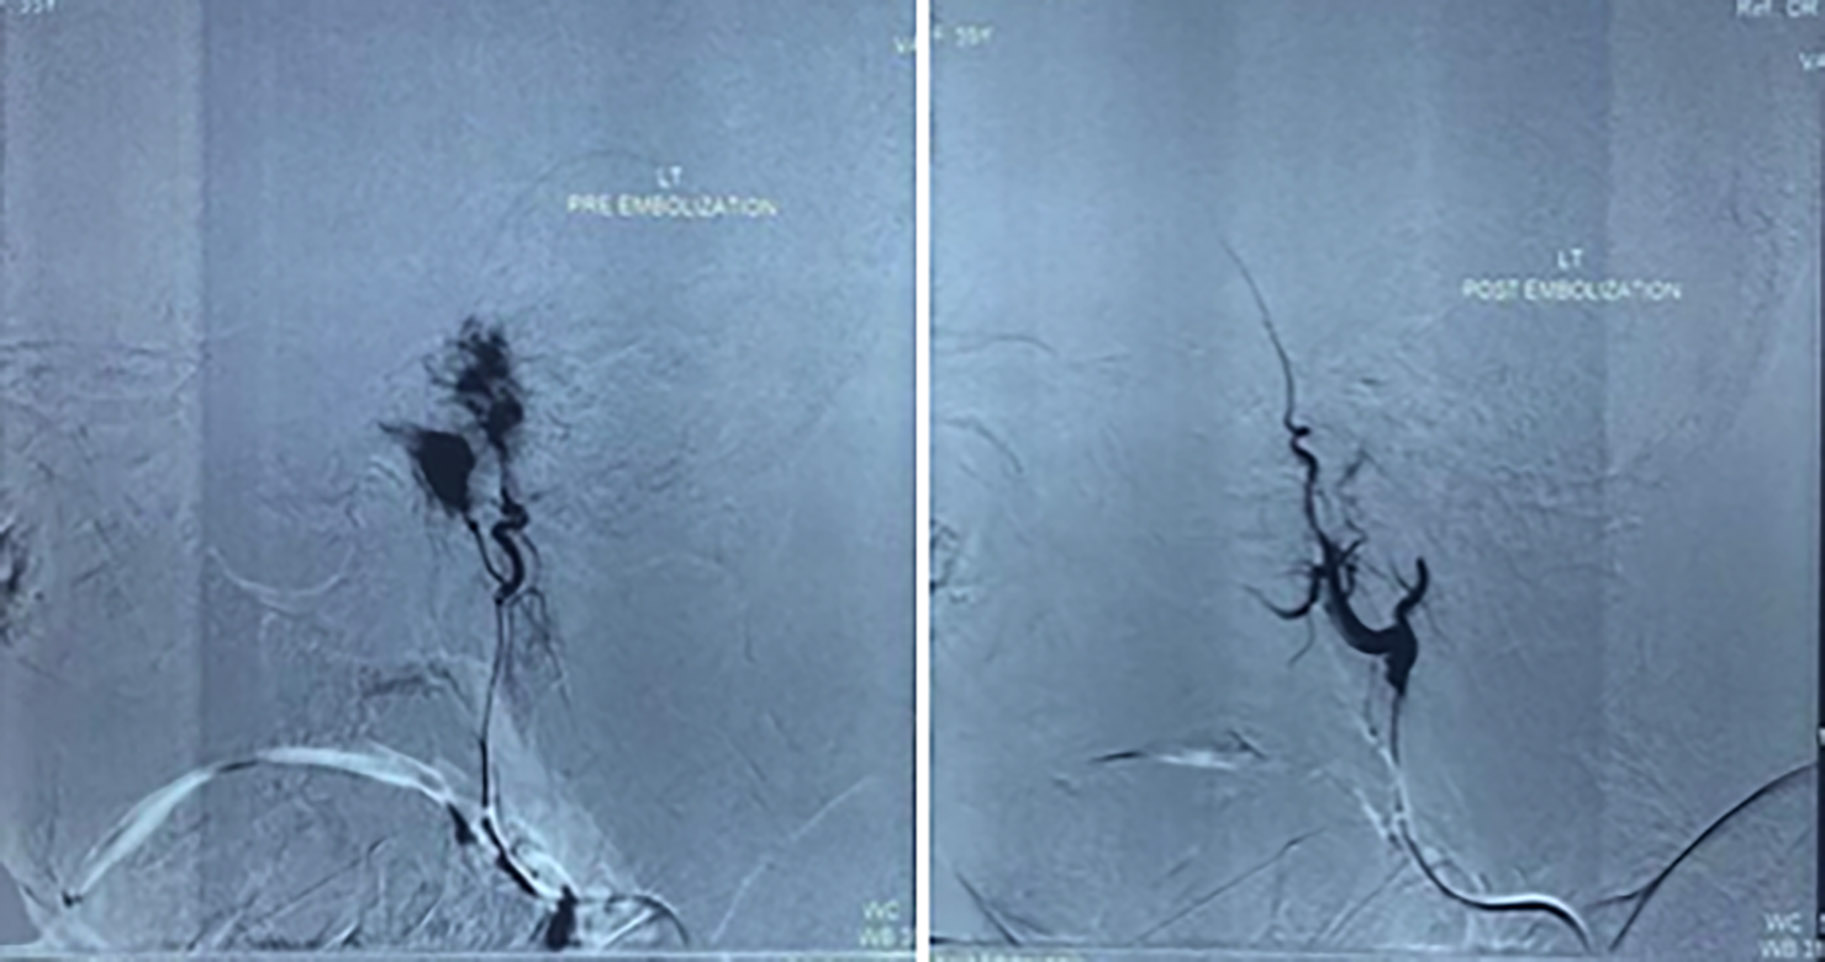

Figure 2: Pre-embolisation angiogram (left) identifying left ascending pharyngeal and posterior auricular arteries as the main feeding vessels. Post-embolisation angiogram (right) shows no flushing.

Selective angiograms were performed, which revealed 80% of the tumour supply from left ascending pharyngeal and posterior auricular arteries and 20% supply from branches of the internal maxillary artery. Subsequently, feeding vessels were super selectively cannulated using a 2.7 Fr microcatheter. Post-embolisation angiogram revealed complete embolisation of the tumour blush. (Figure 2).